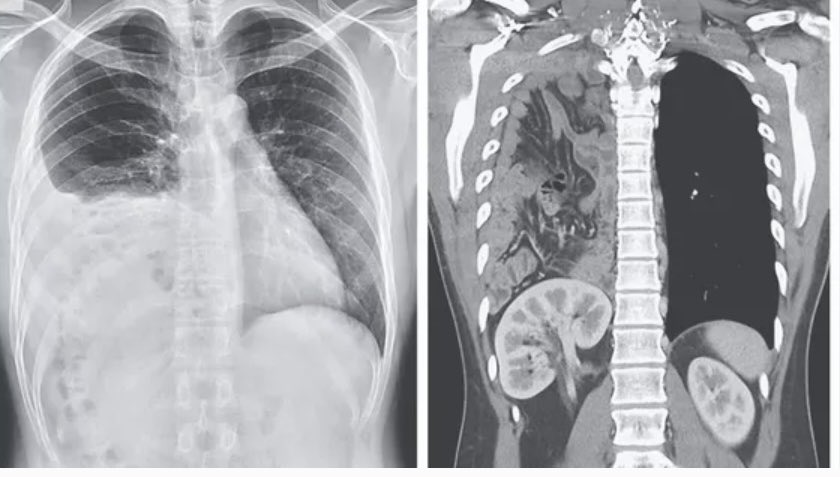

WB-DW MRI or FDG PET/CT for myeloma response? This review breaks down strengths, pitfalls, and standardized criteria (MY-RADS & Deauville). Learn how to integrate both for accurate posttreatment assessment and improved confidence. bit.ly/4viX1Wi